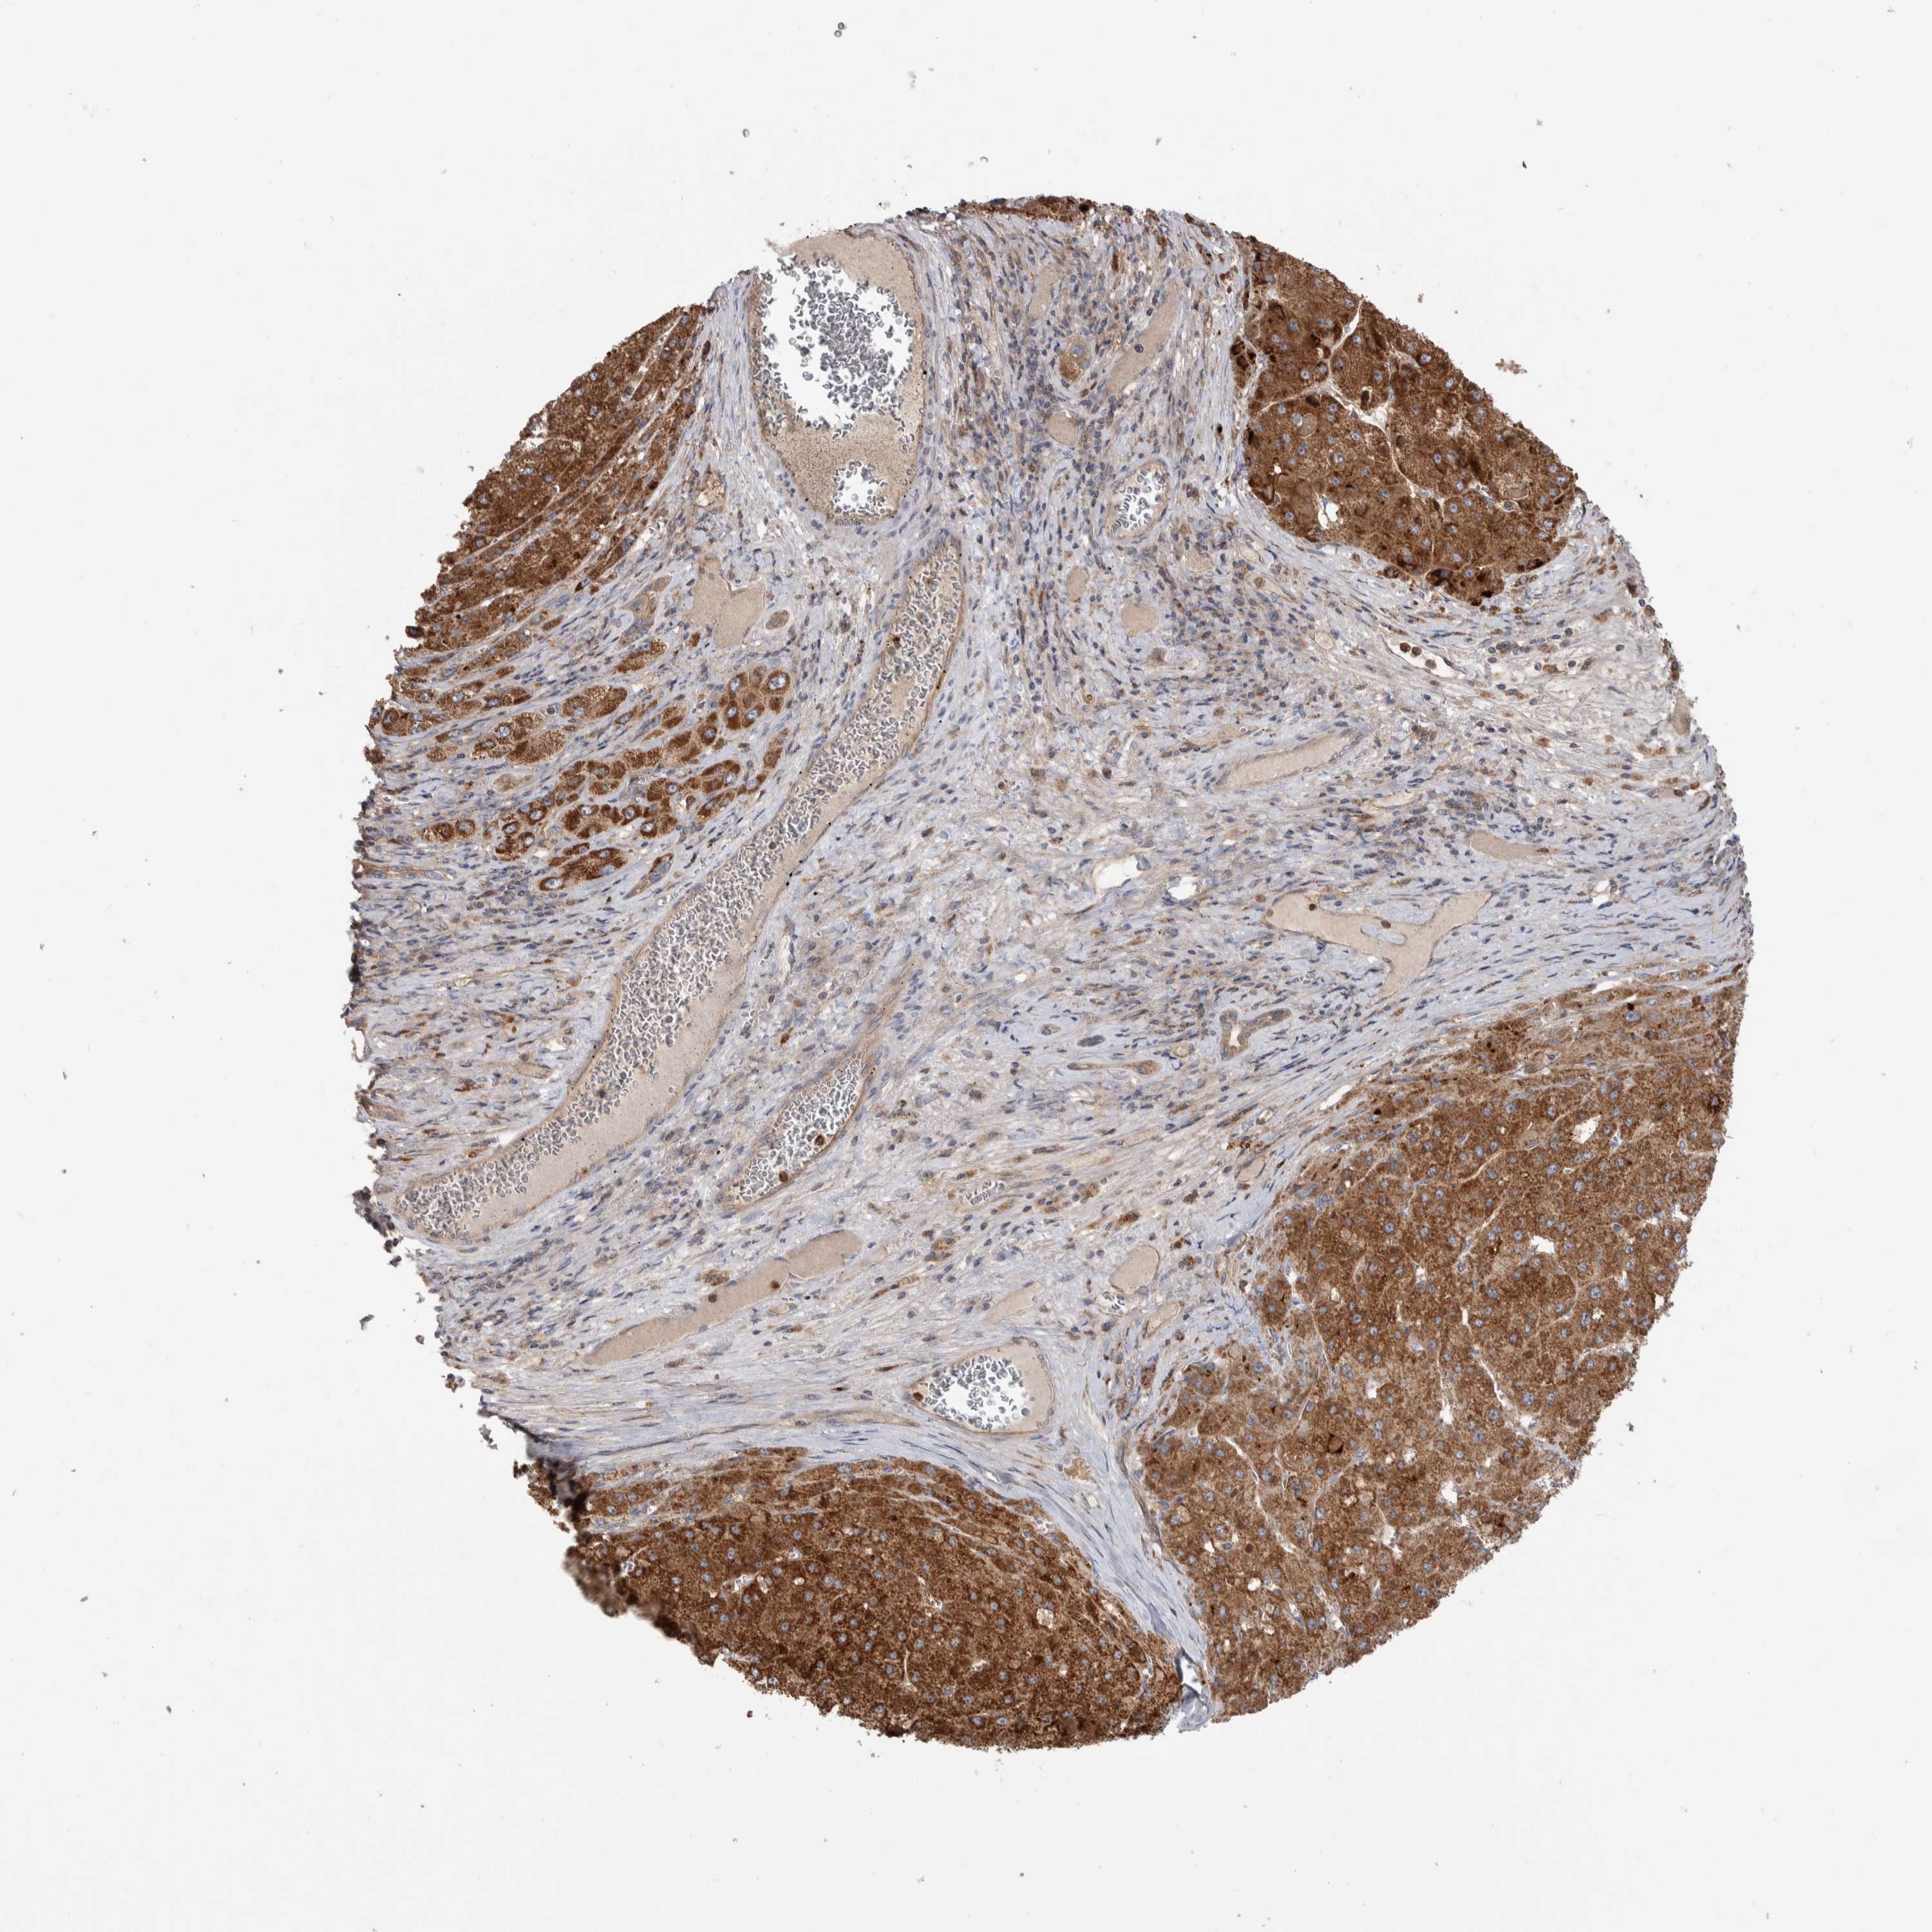

LIVER CANCER - Protein expressioni

A mouse-over function shows sample information and annotation data. Click on an image to view it in a full screen mode. Samples can be filtered based on level of antibody staining by selecting one or several of the following categories: high, medium, low and not detected. The assay and annotation is described here.

Note that samples used for immunohistochemistry by the Human Protein Atlas do not correspond to samples in the TCGA dataset.

Antibody stainingi

Antibody staining in the annotated cell types in the current human tissue is reported as not detected, low, medium, or high, based on conventional immunohistochemistry profiling in selected tissues. This score is based on the combination of the staining intensity and fraction of stained cells.

Each image is clickable and will lead to virtual microscopy that enables deeper exploration of all samples and also displays staining intensity scores, fraction scores and subcellular localization as well as patient and tissue information for each sample.

Antibody HPA023840

Antibody CAB012245

Staining

High

Medium

Low

Not detected

Intensity

Strong

Moderate

Weak

Negative

Quantity

>75%

75%-25%

<25%

None

Location

Nuclear

Cytoplasmic/membranous

Cytoplasmic/membranous,nuclear

Cholangiocarcinoma

Carcinoma, Hepatocellular, NOS